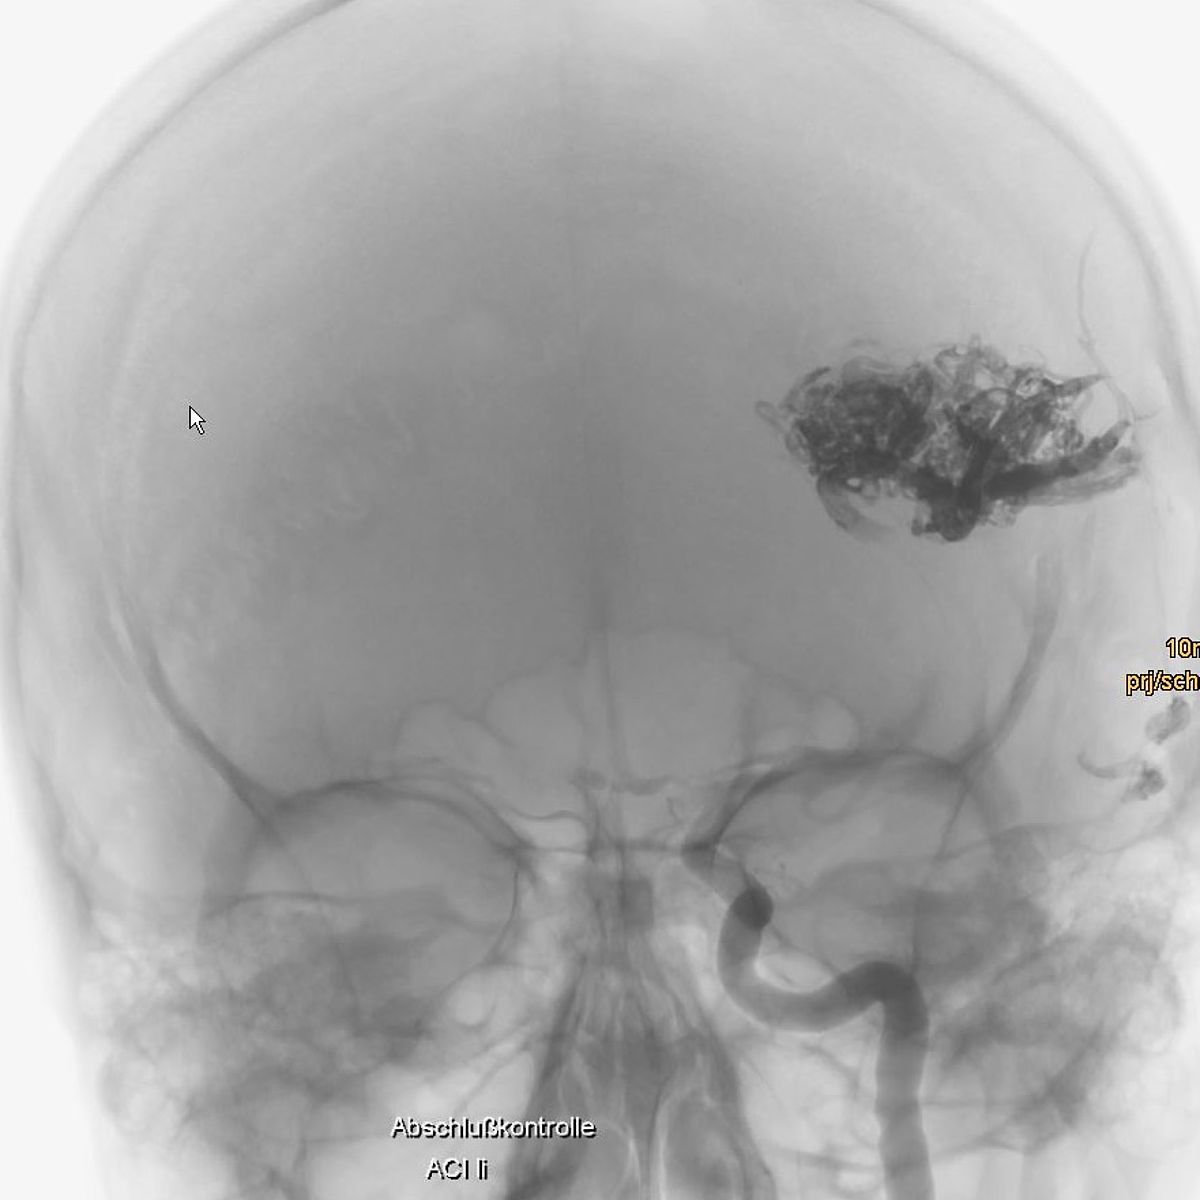

Gefäßmissbildungen und -tumore können zu Blutungen führen, aufgrund ihrer Größe lokale Probleme verursachen oder auch nur rein ästhetisch störend sein.

Die Neuroradiologie ist bei der Diagnostik solcher Gefäßveränderungen mit Computertomographie, Kernspintomographie und vor allem der Angiographie gefragt.

Im Rahmen der interventionellen Therapie sind endovaskuläre und perkutane Injektionen mit verödenden Substanzen, Gewebe- und Gefäßkleber möglich.